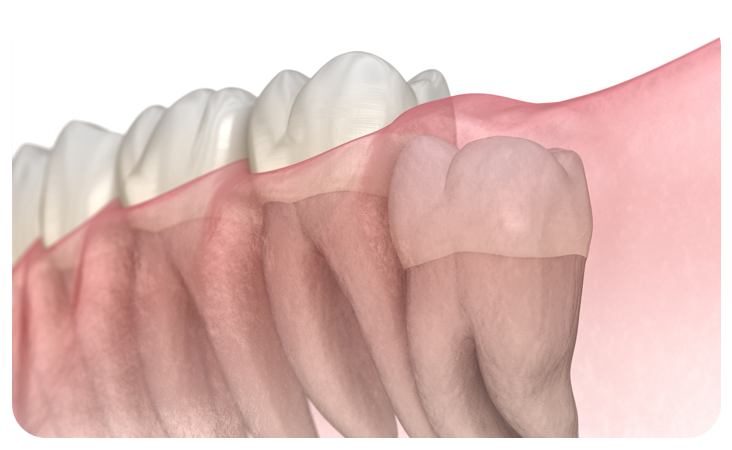

매복사랑니란?

사랑니가 완전히 맹출 되지 않고 잇몸 아래에 묻혀있는 형태의 사랑니를 매복 사랑니라고 합니다.

매복 사랑니는 함치성낭종, 염증 유발, 턱뼈 손상 등의 문제를 유발할 수 있어 발치해주는 것이 좋습니다.

부분매복